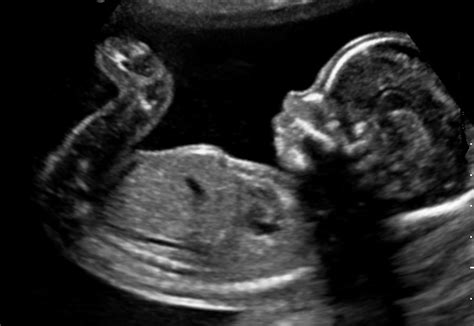

L'evoluzione tecnologica ha trasformato radicalmente il campo della diagnostica prenatale, permettendo di indagare precocemente il benessere fetale. L'analisi genetica avanzata è oggi uno strumento fondamentale per individuare malattie monogeniche fetali, inclusa la beta-talassemia e la sordità congenita, tramite tecniche di sequenziamento di nuova generazione (NGS). Tale indagine è indicata a partire dalla decima settimana di gestazione, specialmente in presenza di rischio genetico accertato, anomalie riscontrate all'ecografia o in caso di età paterna avanzata.

La provincia di Ravenna vanta centri di riferimento, come il Ravenna Medical Center - GVM Care & Research, dove l'Ostetricia si dedica all'assistenza completa della donna durante la gravidanza, il parto e il puerperio. L'assistenza non si limita al controllo mensile della salute materna, ma si avvale di tecnologie avanzate come la cardiotocografia esterna, un esame non invasivo che permette di monitorare il battito cardiaco fetale e le contrazioni uterine, essenziale per valutare il benessere del feto e identificare precocemente eventuali anomalie.

Inoltre, la valutazione della modalità di parto viene condotta con un'attenzione particolare alle pazienti pre-cesarizzate o sottoposte in passato a interventi chirurgici sull'utero. L'esperienza clinica consente di offrire procedure specialistiche come il rivolgimento per manovre esterne, garantendo un'assistenza che copre ogni aspetto, dalla diagnosi ecografica di secondo livello (con certificazione della Fetal Medicine Foundation per la misurazione della traslucenza nucale) all'utilizzo di tecniche tridimensionali per lo studio morfologico del volto e della colonna vertebrale fetale.